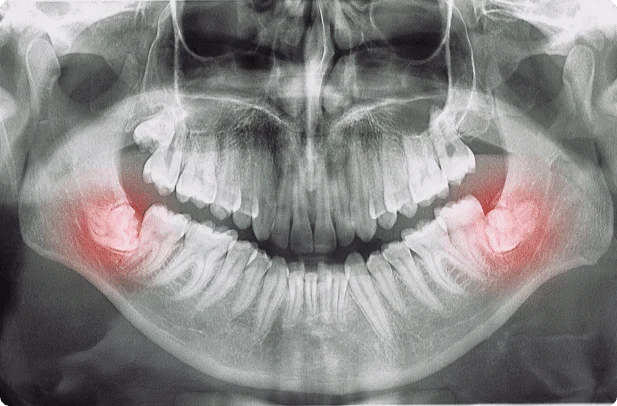

Wisdom teeth are the third set of molars that typically emerge between the ages of 17 and 25. While some people may have no issues with their wisdom teeth, others may experience pain, infection, and other complications. This is because wisdom teeth often do not have enough room to fully emerge or properly align with the rest of the teeth.

When should a wisdom tooth be removed?

It is important to monitor your wisdom teeth for signs of potential problems. Some common symptoms include:

Wisdom teeth are typically removed in the late teens or early twenties because there is a greater chance that the teeth’s roots have not fully formed and the bone surrounding the teeth is less dense. These two factors can make extraction easier, as well as making the recovery time much shorter.

To remove a wisdom tooth, our doctors first needs to numb the area around the tooth with a local anesthetic. He can use additional medication to safely sedate you during the extraction if you are feeling nervous about the procedure. Since the impacted tooth may still be under the gums and imbedded in your jaw bone, our doctors will need to remove a portion of the covering bone to extract the tooth. To minimize the amount of bone that is removed with the tooth, he will often “section” your wisdom tooth so that each piece can be removed through a small opening in the bone. Wisdom tooth surgery typically takes less than an hour and patients can usually resume their normal activities within a few days.